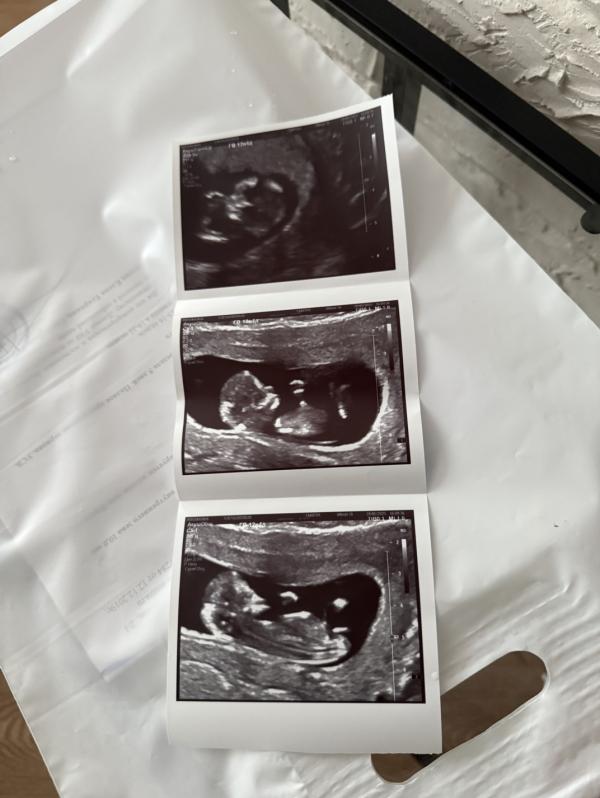

12 недель: что ждать от первого скрининга?

12 недель мой первый скрининг❤️🤗

Это последние фотки, когда он полностью поместился на узи 😍